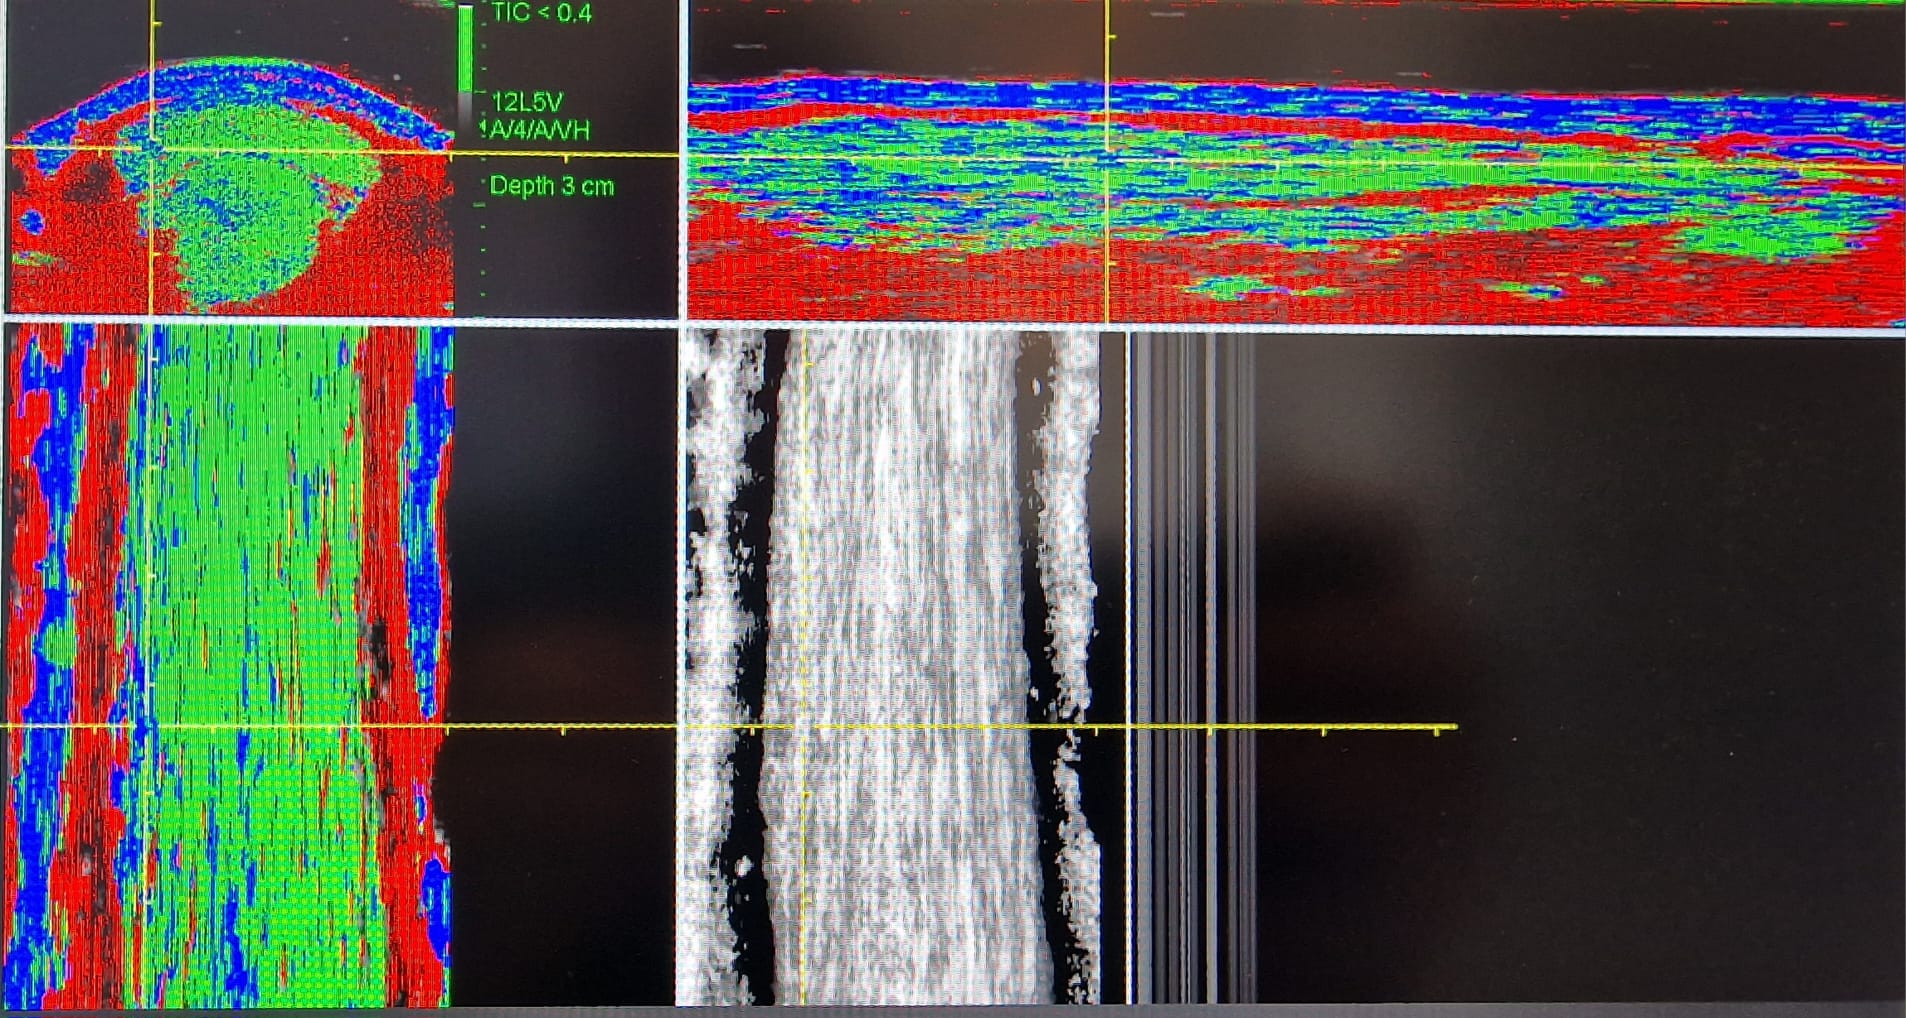

De technologie van de UTC scan is gebaseerd op de techniek van echografie, het verschil is alleen dat de probe gekoppeld zit aan een soort computer bewogen arm. Hierdoor is er geen verschil meer in de opnametechniek tussen verschillende scans van dezelfde pees, aangezien de probe altijd op dezelfde wijze (snelheid en richting) de pees in beeld brengt. Wanneer de probe de pees scant wordt er om de 0,2 mm een beeld gemaakt wat direct door de computer verwerkt wordt. Zo kan er van één scan zowel een dwars- als een lengtedoorsnede gemaakt worden. Door de computerverwerking kan de pees in elke gewenste richting bekeken worden wat een 3D beeld van de pees geeft.

Naast het goed in beeld brengen van de pees kan de software ook de integriteit (kwalitatieve toestand) van de pees in beeld brengen. Hiermee kunnen we nog beter zien in hoeverre de pees weer belast kan worden na bijvoorbeeld een blessure. Een ander groot voordeel hiervan is dat we een kleine overbelasting met deze techniek ook al kunnen zien. Zo’n subtiele verandering in de pees kan dan nog gemakkelijk herstellen naar de oorspronkelijke kwaliteit, terwijl er bij een verscheuring nooit meer de kwaliteit van het originele weefsel terugkomt. Het revalidatie plan is met deze techniek nóg preciezer te bepalen.

De software kan de verschillende types weefsel in de pees voorzien van een kleurcode:

- Groen voor normaal gerangschikte peesbundels

- Blauw voor meer golvende peesbundels

- Rood voor fibrillaire (kleinere/onvolwaardige) bundels

- Zwart voor met name vocht

Aan elk van deze weefsels kan een percentage gebonden worden. Hierdoor heb je naast een duidelijk beeld van de kwaliteit van de pees ook een meetbaar resultaat, dat vergeleken kan worden met eerder gemaakte scans van het paard.